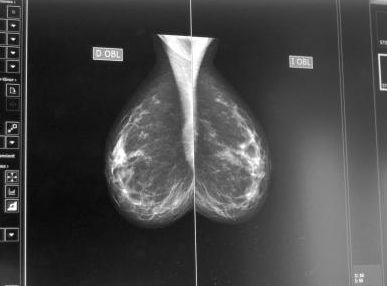

Mamografías con menos dosis de radiación y más calidad de imagen

El Grupo Hospitales Miguel Domínguez ha renovado sus equipos de digitalización de estudios radiológicos, en colaboración con la marca Agfa Healthcare, con el objetivo de mejorar la calidad de las imágenes obtenidas y reducir las dosis de radiación en los pacientes en cada prueba.

Concretamente, el grupo sanitario ha invertido en la compra de nuevos chasis para el mamógrafo, de yoduro do cesio estructurados en forma de aguja. Esta tecnología permite obtener una imagen de hasta 20 megapíxeles y reducir la dosis real de radiación entre un 20 y un 40%.